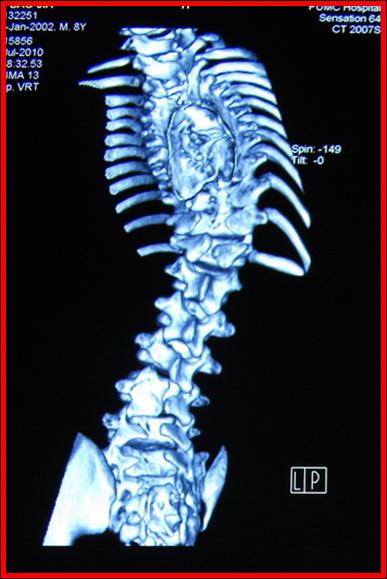

术前CT 显示脊髓纵裂畸形

术前CT